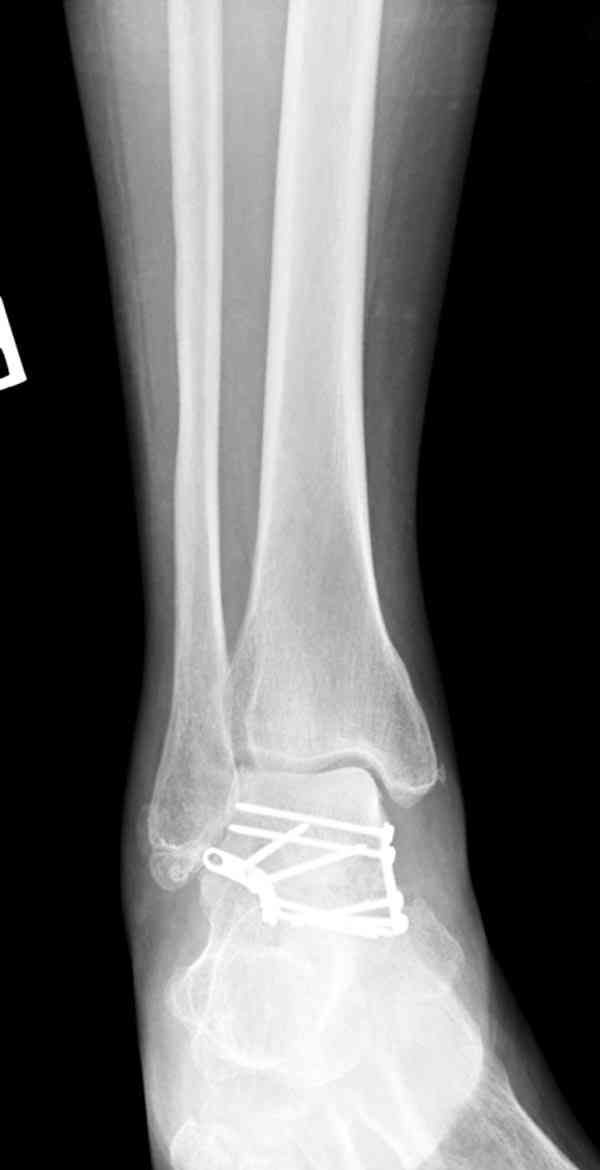

И второй случай из недавней ташкентской практики, (извините за качество ренгенограммы и только в одной проекции) случай падения с высоты (кстати моего друга - известного киноактера) - открытый

смещенный перелом тарана, с переломом переднего края дистального эпиметафиза большеберцовой кости.

При поступлении в приемной сделана первичная обработка с ушиванием открытой латеральной раны и вытяжением за пятку.

Из-за отсутствия времени пришлось оперировать на второе утро, из материала, что имеем на месте, фиксирован двумя шурупами, а третий-это контур сломанного жойстика в 4 мм. На дистальный медиальный конец тибиа antiglide 3.5 мм пластина. Через пару дней выписан и несмотря на предупреждение, самостоятельно начал нагрузку в 4 недели, время не ждет, снимается в боевике в Росийской Федерации.